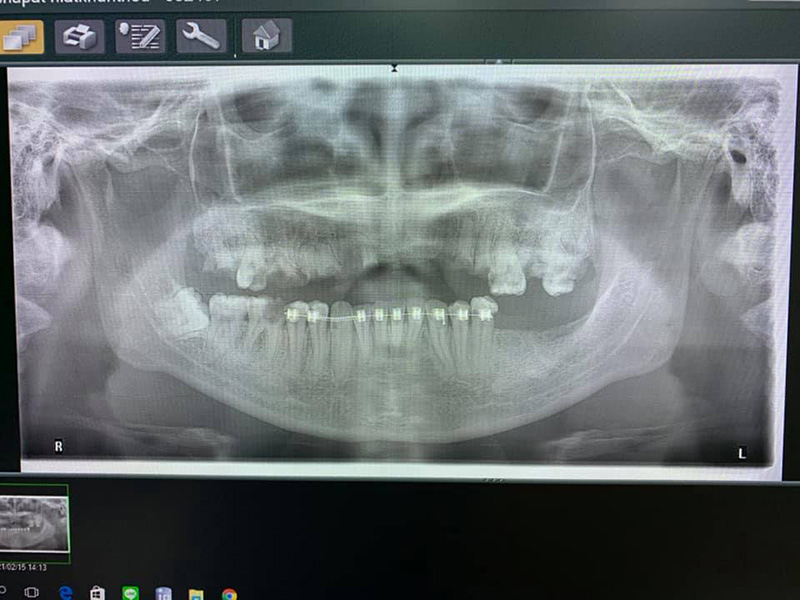

วันที่ 16 กุมภาพันธ์ 2564 เพจ Doctor กล้วย ได้มีการโพสต์เตือนภัยคนติดเหล็กดัดฟันแฟชั่น จนต้องถอนเกือบทั้งปาก โดยคุณหมอ เผยว่า เคสนี้เป็นคนไข้หญิง อายุ 30 ปี มาถอนฟันด้วยอาการปวด และมีหนองที่ฟันบน ตรวจพบว่า ฟันบนผุทั้งหมด ส่วนใหญ่เหลือแต่รากฟัน ดูจากฟิล์มเอกซเรย์ แทบไม่เหลือให้หมอรักษาแล้ว ฟันล่างผุเละ แถมยังติดเครื่องมือจัดฟันอยู่ หมอดูรู้เลยไม่ใช่ฝีมือหมอฟันแน่นอน จากการติดแบบมั่ว ๆ

#คนไข้ติดเหล็กดัดฟัน แบบไม่มีการเตรียมช่องปาก มานานเป็นปีแล้ว ฟันบนต้องถอนเกือบทั้งหมด ฟันล่างผุเละ และหินปูนหนามาก สรุปเกือบหมดปากที่ต้องทำฟันปลอมใส่ ทั้ง ๆ ที่อายุยังน้อย ดูกันนะ นี่คือผลของความ อยากติดเหล็กดัดฟัน โดยไม่คิดถึงผลเสียที่จะเกิดกับตัวเองไปตลอดชีวิตที่ไม่มีฟันเคี้ยวข้าว #อย่าหาทำ #จัดฟันแฟชั่นอันตราย แอดขอเตือน ขอบคุณข้อมูลและภาพจาก Doctor Supachai Sk ที่ช่วยส่งเคสมาเตือนสังคม